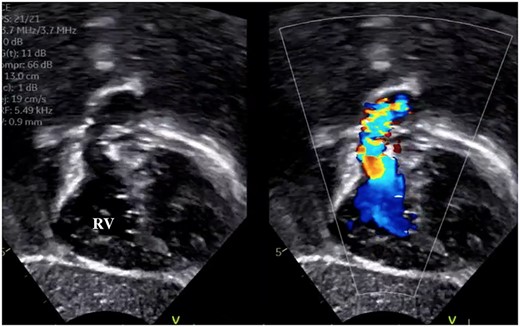

A male infant with TGA accompanied by Shaher Type 4 coronary anatomy underwent ASO at 5 days of age. Intraoperatively, the right ventricular outflow tract was injured during the RCA separation to obtain the mobilization and repaired using an autologous pericardial pledget, resulting in postoperative subvalvular PS. Follow-up evaluation showed relief of the subvalvular PS, but pulmonary valve stenosis, main pulmonary artery (PA) stenosis and right PA stenosis progressed because of the subvalvular jet. Transthoracic echocardiography showed a trans-right ventricle (RV) outflow peak velocity of 4.5 m/s, a systolic pressure gradient of 83 mmHg and a right ventricular fraction area change of 46.4% (Fig. 1). Cardiac catheterization showed a right ventricular pressure of 97 mmHg, a right ventricular/left ventricular pressure ratio of 0.99 and a systolic pressure gradient across the right ventricular outflow of 91 mmHg. The diameter of the pulmonary valve annulus was 6.1 mm (63.6%) (Fig. 2). Three-dimensional-computed tomography showed that the distance between the RCA and the tricuspid valve was 7 mm (Fig. 3).

Preoperative transthoracic echocardiography showing right ventricular outflow tract narrowing and jet flow.